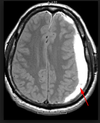

What is the most common cause of a subarachnoid hemorrhage?

Where is it most likely to occur?

What are some associations?

Rupture of berry aneurysm. (*lacks a media layer –> weak wall –> sacular outpouching)

Other causes: AV malformations, anticoagulated state

Most frequently in anterior circle of Willis at branch points of the ACA.

Associated w/Marfan and autosomal dominant polycystic kidney disease (ADPKD).